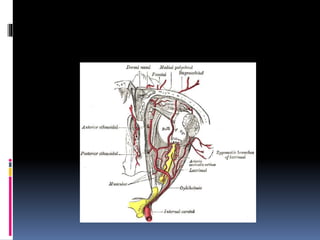

FACIAL NERVE:-